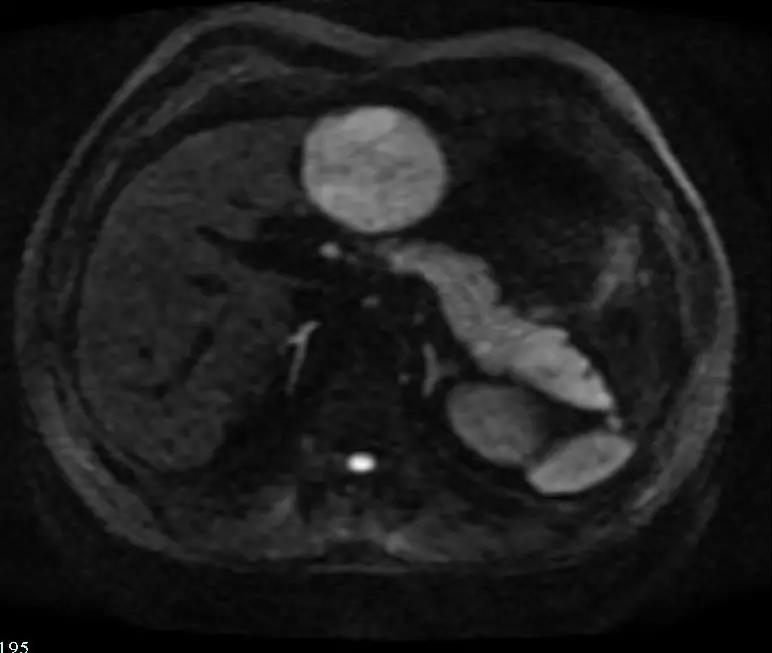

肝胆 MR 平扫弥散+增强:左肝内占位,肝癌首先考虑,请结合临床。附见:双肾囊肿。

弥散相